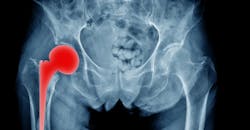

After reviewing thousands of case studies going back 25 years across six countries, researchers at the University of Bristol say they indicate that eight out of 10 total knee replacements (TKRs) and six out of 10 total hip replacements (THEs) will still be in place after 25 years. Despite doing more than two million hip and knee replacements over the past 16 years, British doctors were unable to give patients a fact-based estimate of how long they might last. Previous studies have been based on much smaller samples. At best, UK doctors could only tell patients how long replacements were designed to last, rather than referring to actual evidence from patients’ experiences of joint replacement surgery.

Hip and knee replacements are two of the most common and effective forms of surgery. Yet even in the best-case scenarios, they will ultimately fail due to infections, fractures, normal wear-and-tear, and reactions to wear particles. In many of these cases, patients require revision surgery which is more prone to failure, associated with recoveries, and more expensive than primary surgery.

Of the total hip replacements, 89% were found to last 15 years, 70% lasted 20 years, and 58% lasted 25 years.

The survival outcomes for total hip replacements were impressive: Almost nine out of 10 lasted 15 years, seven out of 10 were in place at 20 years, and almost six out of 10 at 25 years.